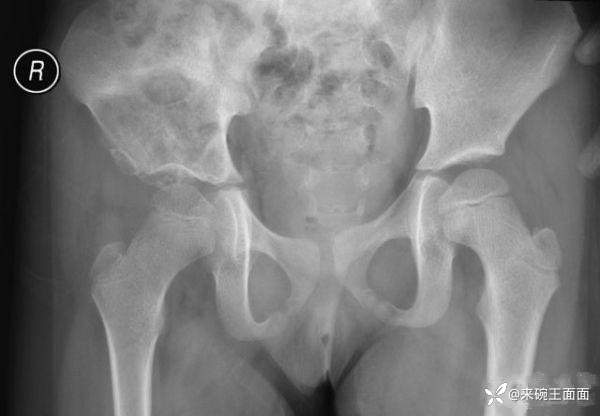

性别:女

年龄:6岁

主诉:跛行3年,右髋活动受限4月。

详情:右侧髂骨膨胀性骨质破坏,边缘有硬化,骨皮质不完整,有骨膜反应,可见边缘不清、形态不规则钙化、骨化影。